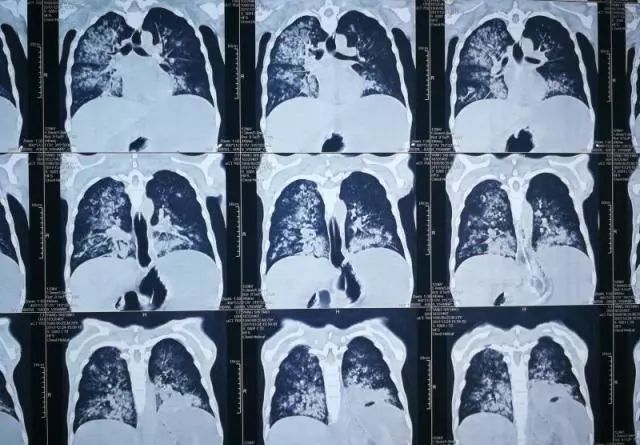

CT影像可见,小浩腹腔内大量积液,胸腔内感染非常严重

当时正在院外开会的王峰以最快速度赶回医院,检查后发现小浩感染突然加重,因感染导致膈肌穿孔,腹腔内的脓液进到了胸腔和气管中。小浩被迅疾转入ICU进行气管插管和吸痰,同时进行腹腔脓液的引流。三天后,胃肠外科李元新主任团队为小浩做了艰难的手术,进行了腹腔引流和膈肌修补,术后当日下午因凝血功能差又发生活动性出血,再次进行急诊手术止血。这次术后,小浩的病情才终于稳定下来,“每天都盼着他们来查房,看到他们就觉得救星来了。”小浩的父亲说。